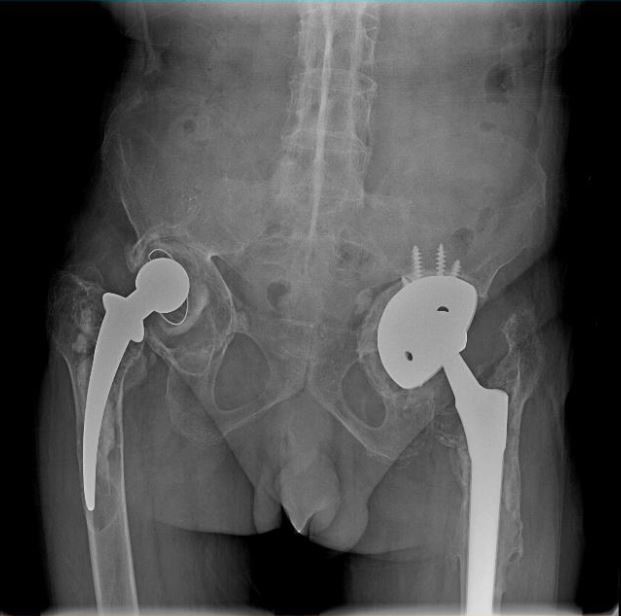

男 70岁

双侧股骨头置换术后

双侧股骨头置换术后复查

通过全景拼接图像可以清晰显示双下肢对比情况,为术后评估提供更多影像学资料。